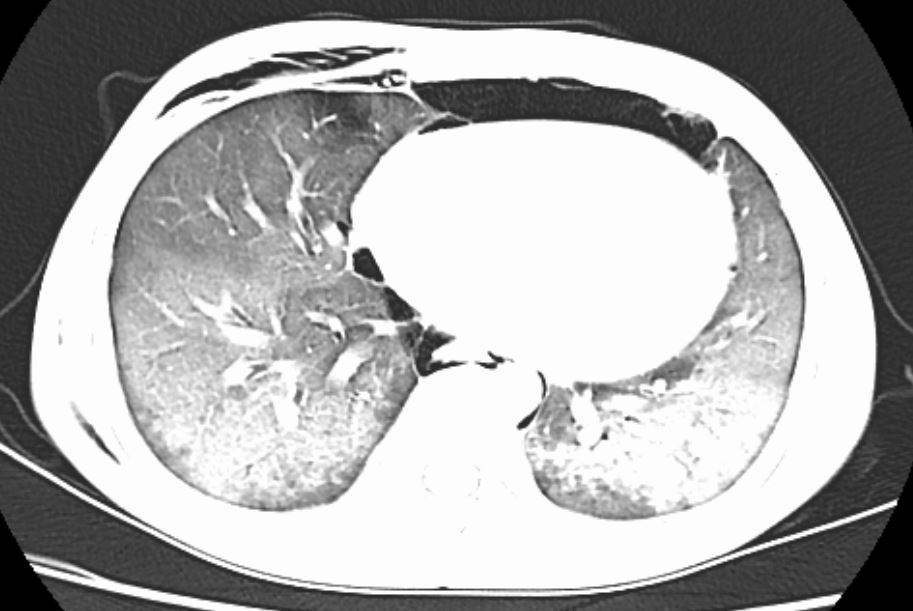

2026年2月14日,农历腊月二十七,春节将至,11岁的男孩小睿(化名)因“发热、腹泻、呕吐、皮疹、结膜充血2天”被紧急送入玉林市红十字会医院儿科。入院后不久,患儿病情急转直下,突然出现胸痛、气促、呼吸困难、口唇面色紫绀,紧急完善相关检查提示重症肺炎、纵膈气肿、皮下气肿,急性呼吸窘迫综合征(ARDS),生命体征极不稳定。儿科医疗团队紧急联系相关科室急会诊,在超声引导下急诊行纵隔气肿穿刺置管引流术,术后胸痛有所缓解,但气促仍进行性加重,提示肺部病变在持续恶化,必须立即行气管插管、呼吸机辅助呼吸。年味正浓的病房,瞬间变成了争分夺秒的“战场”。

肺部影像

作为春节值守的医护团队,他们深知,此刻每一秒都关乎生命。科室迅速启动重症救治预,儿科主任邓燕艺及副主任杨栋对患儿进行评估后,果断为小睿进行气管插管,护理团队实行24小时专人守护,时刻监测生命体征,警惕病情变化,时不时与患儿说话,触摸他的手心,安抚孩子情绪。